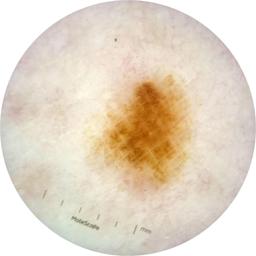

ISIC_9472333

Information

2057 x 2057

Clinical

Field Value

acquisition_day 230

age_approx 65

anatom_site_1 Trunk

anatom_site_2 Anterior trunk

anatom_site_general anterior torso

concomitant_biopsy False

diagnosis_1 Benign

diagnosis_confirm_type single image expert consensus

family_hx_mm True

fitzpatrick_skin_type I

image_manipulation instrument only

image_type dermoscopic

lesion_id IL_9967494

patient_id IP_4296977

personal_hx_mm True

sex female